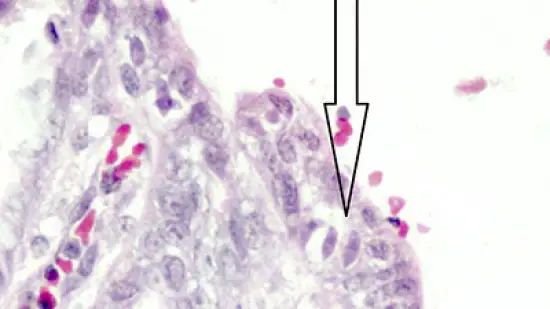

Semana de 25-Jul-2023

Qual protozoário está sendo indicado pela seta? Está dentro da mucosa do intestino delgado de um leitão com diarreia.